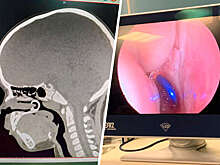

В Чувашии врачи спасли ребенка, вдохнувшего серьгу для пирсинга

Дети

24 октября 2023